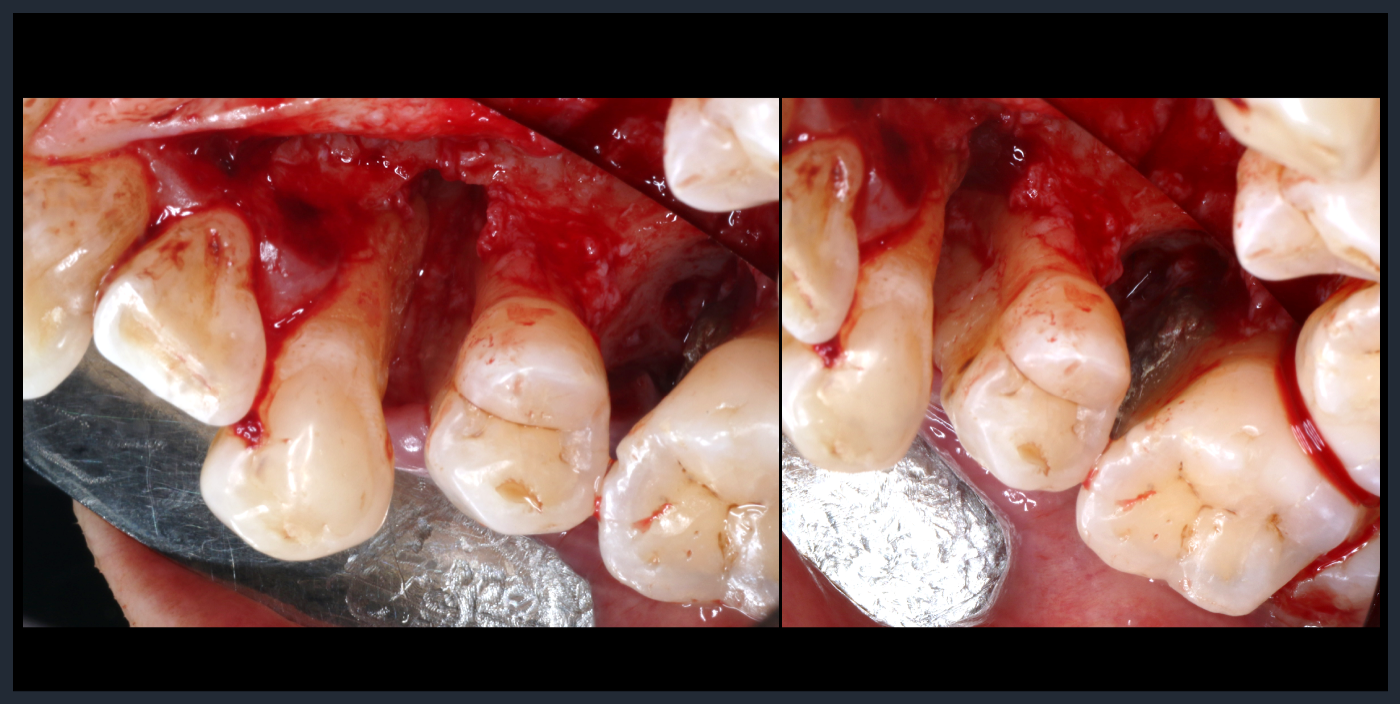

フラップ形成後、多量の縁下歯石。

フラップ形成後、多量の縁下歯石。